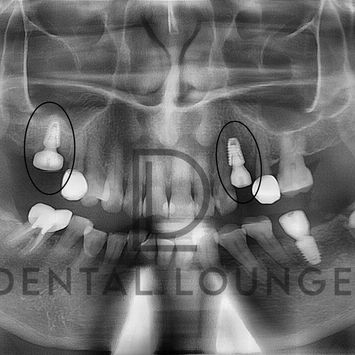

Implant Placement at #24 & #16 with Internal Sinus Lift

Patient satisfied with current #36 implant crown; presented for implant surgery at missing #24 and #16 sites.

Missing #24 and #16 requiring implant-supported replacement

CBCT confirmed adequate ridge height with need for internal sinus lift at #16

Dentium Superline III 4.5 × 8.0 mm implant placed

5.5 mm (M) healing abutment attached

Dentium Superline III 5.0 × 8.0 mm implant placed

8.5 mm (M) healing abutment attached

Post-op CBCT confirmed ideal implant angulation and positioning

Sinus lift successful with intact membrane and no perforation